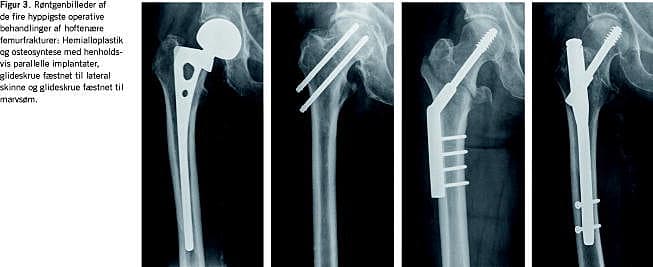

I Referenceprogrammet anbefales intern fiksering ved alle collumfrakturer, fraset hos patienter, der er over 75 år og har en disloceret collumfraktur, hvor der anbefales en hemialloplastik [1]. Gennemgangen af litteraturen gør det muligt at nuancere disse anbefalinger (Figur 1 og Figur 3 ). Således bør en alloplastik tillige overvejes ved den udislocerede fraktur med over 20° posterior frakturvinkling, hvor risikoen for komplikationer efter intern fiksering er øget [13]. For alloplastik taler også tilstedeværelsen af osteoporose eller artrose [1, 27]. For intern fiksation taler derimod anatomisk reposition og et stort caputfragment [26]. Osteosyntese bør også overvejes hos de ældste/demente patienter, som ikke forventes at kunne overholde bevægerestriktionerne ved en hemialloplastik, eller som dårligt tåler den større kirurgiske procedure herved [33]. Om calcar er intakt er dertil essentielt for valg af osteosyntesemetode [18, 27].

Den pertrokantære fraktur behandles hyppigst med reposition og intern fiksering med en glideskrue og lateral skinne fæstnet med 3-4 skruer i femurskaftet (Figur 2 og Figur 3). AVN ses sjældent. Frakturskred medfører dog reoperation hos 4-12%, afhængigt af frakturtype og operationsmetode [1, 8, 14-17, 35]. Frakturskred skyldes inadækvat reposition og placering af glideskruen, som inden for de første postoperative måneder kan medføre, at caputfragmentet dislocerer i varus, lateraliseres og/eller teleskoperes ned i femurmetafysen med risiko for glideskrueperforation af caput (cut-out ). Dette medfører smerte og forkortet benlængde.

Forfatterne finder, at Referenceprogrammet fra 1999 med fordel kan opdateres med anbefalinger af den i nærværende artikel skitserede mere præcise frakturklassificering og operative behandling ud fra de seneste internationale studier (Figur 1-3). Disse nationale retningslinjer bør danne udgangspunkt for ensartede, mere detaljerede afdelingsinstrukser, så resultatet i mindre grad afhænger af geografien, den vagthavende ortopædkirurg og størrelsen af dagsprogrammet.